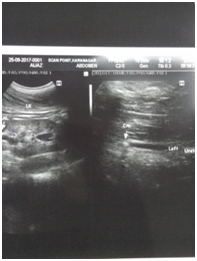

All patients who reported within 1-2 days of ureteric colic were examined, and subjected to Haemogram, KFT, Urine examination, Ultrasound and NCCT Scan (Figure 1&2) to document ureteric calculi at the time of colic with respect to location, side and size of the stone. Age and sex of the patient was noted down and SOADS regime was started for a period of 4 weeks maximum after which this MET was stopped. The routine follow up examination were performed, using the same tools to evaluate the success of the treatment after every week till 4 weeks of study period. Patients were instructed to discontinue the study medication after spontaneous stone expulsion and date of expulsion is to be recorded. For patients without stone in urinary tract on final USG/NCCT but unnoticed stone expulsion, the date of last positive stone status is to be recorded (Figure 3). For the children the dosage of the SOADS regime was half the dosage. Two - three litres of fluid which consists of Lemon juices, Oranges juices and clear water or Tea. This regime was continued for 2 weeks after which again assessment was made and if the stone did not pass then it was continued for another 2 weeks. Treatment was considered successful when stone was expelled within 4 weeks. After 4 weeks, patients who did not pass the stone were advised to undergo minimally invasive surgery depending upon the stone size and location.

Figure 2 Ultrasound showing upper ureteric calculi and uvj calculi.